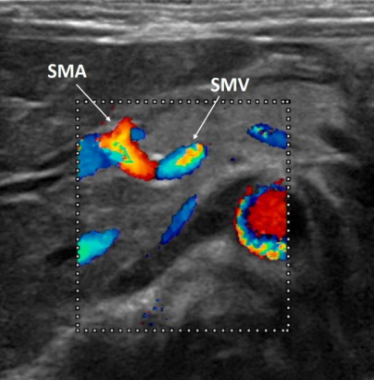

What is the diagnostic test for malrotation with volvulus?

Upper GI contrast study may show duodo-jejunal flexure is more medially placed, USS may show abnormal orientation of the superior mesenteric artery and vein

What does this USS demonstrate?

Malrotation with volvulus